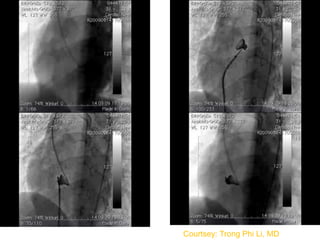

Device selection

 Type of the device

 Size of the device

Determinants of the Device type

 Size of the defect

 Morphology of the defect

Size of the defect

 ADO II : upto 5.5 mm

 Nit Occlud Le VSD coil : upto 8 mm

 ADO I : upto 12 mm

 AAPMVSDO & AMVSD occluder : upto 16 mm

 Modified Membranous VSD occluders

(Lifetech and Shanghai Steel Corp) : upto 19

mm

Sizing the device

 No definite guidelines

 Echo Vs Angio

 LV Vs RV

 APMVSDO: RV side of the defect. Measure in

two planes. Average and add 1

 ADO I: RV side of the defect + 1 or 2 =

Pulmonary end of the ADO I

 ADO II: RV side of the defect + 0.5 to 1 mm